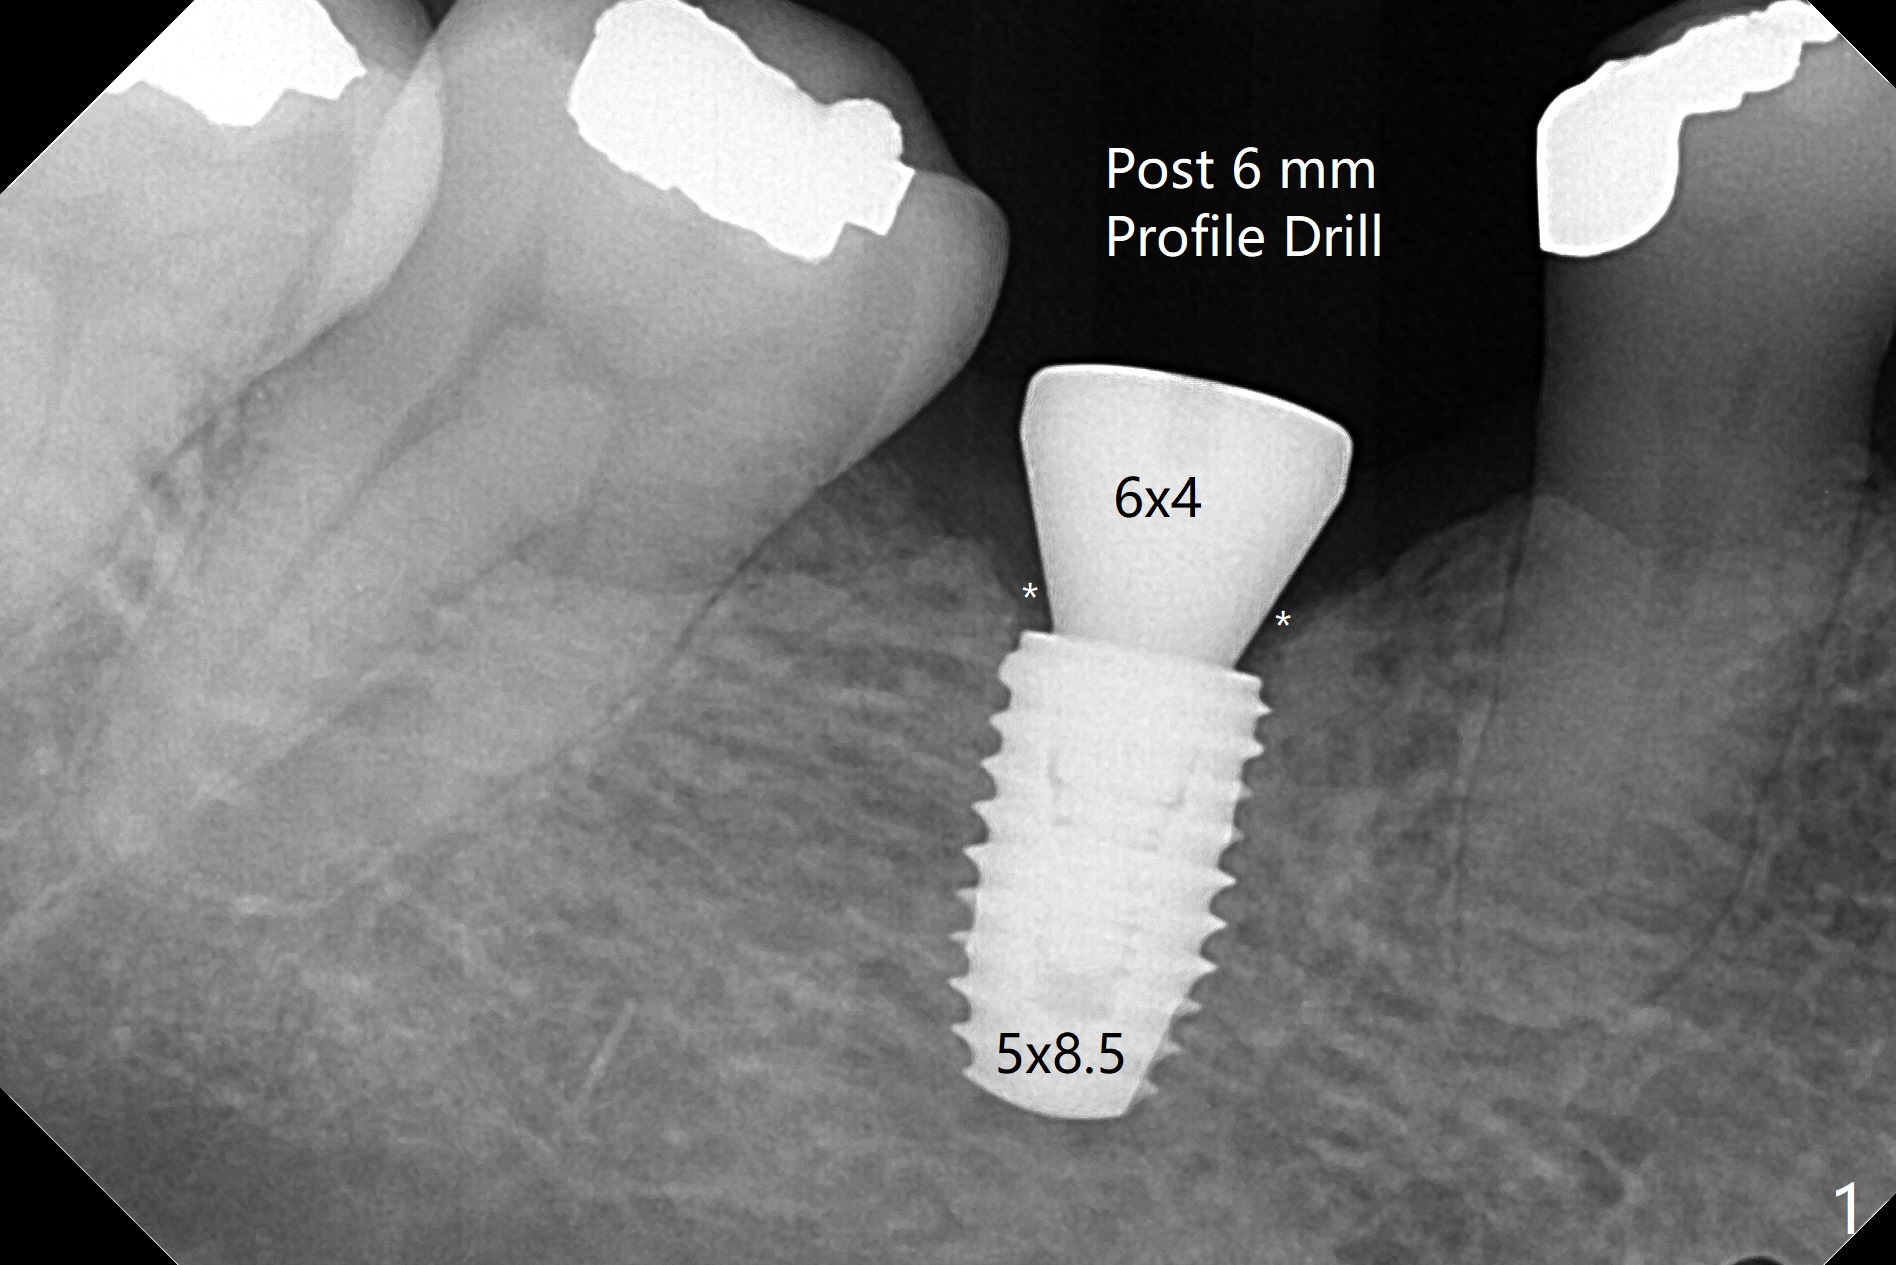

使用导板植入5x8.5毫米植体(图一:相当深)后,使用6毫米Profile钻头。安置6x4毫米愈合基台,后者与近中,远中牙槽嵴之间有距离(*),所以基台就能完全就位(<)。术后即刻使用这种钻头,可以避免二期手术。